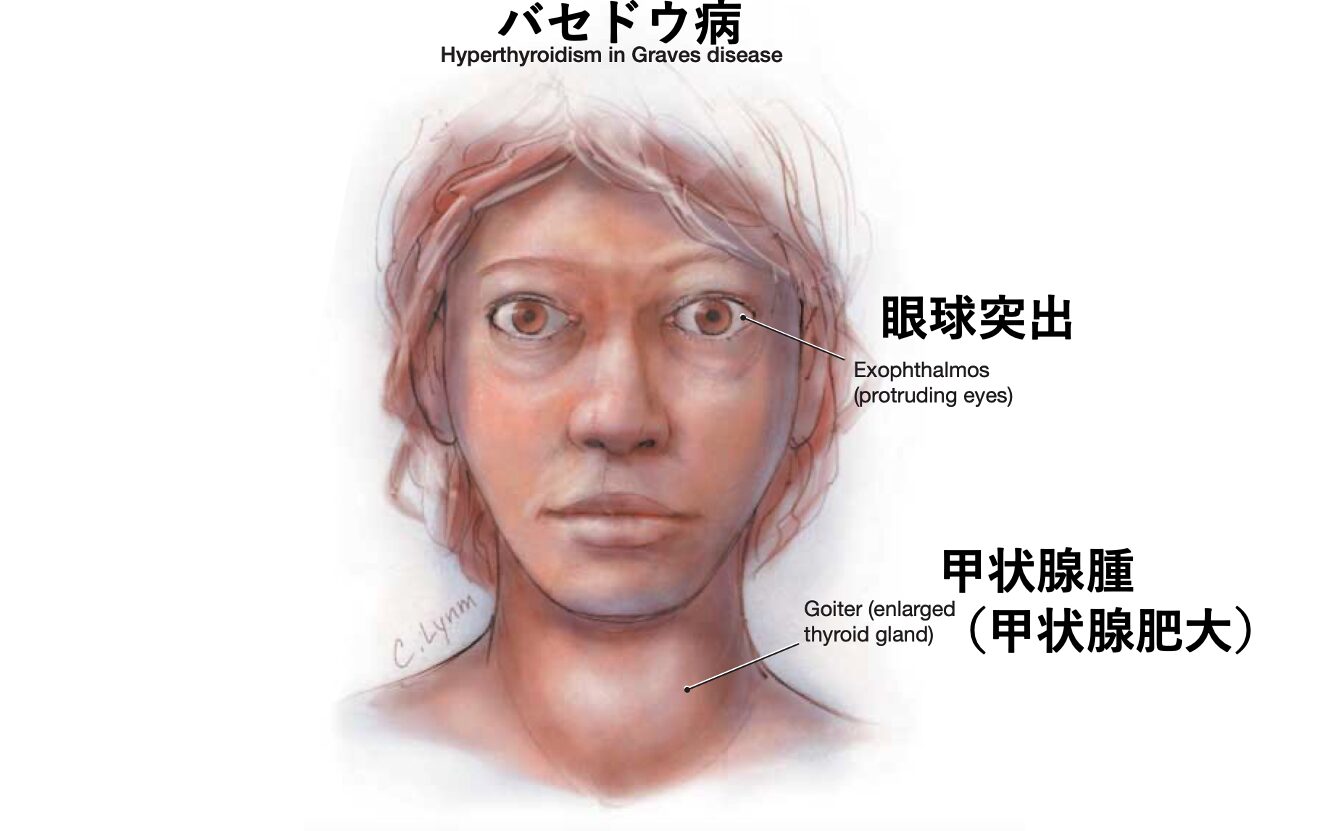

症状

バセドウはドイツのメルゼブルグで診療を行っており、バセドウ病患者の特徴として眼球突出・頻脈・甲状腺腫を報告しました。メルゼブルグで見つけた3徴であることから後にメルゼブルグの3徴と呼ばれるようになりました。